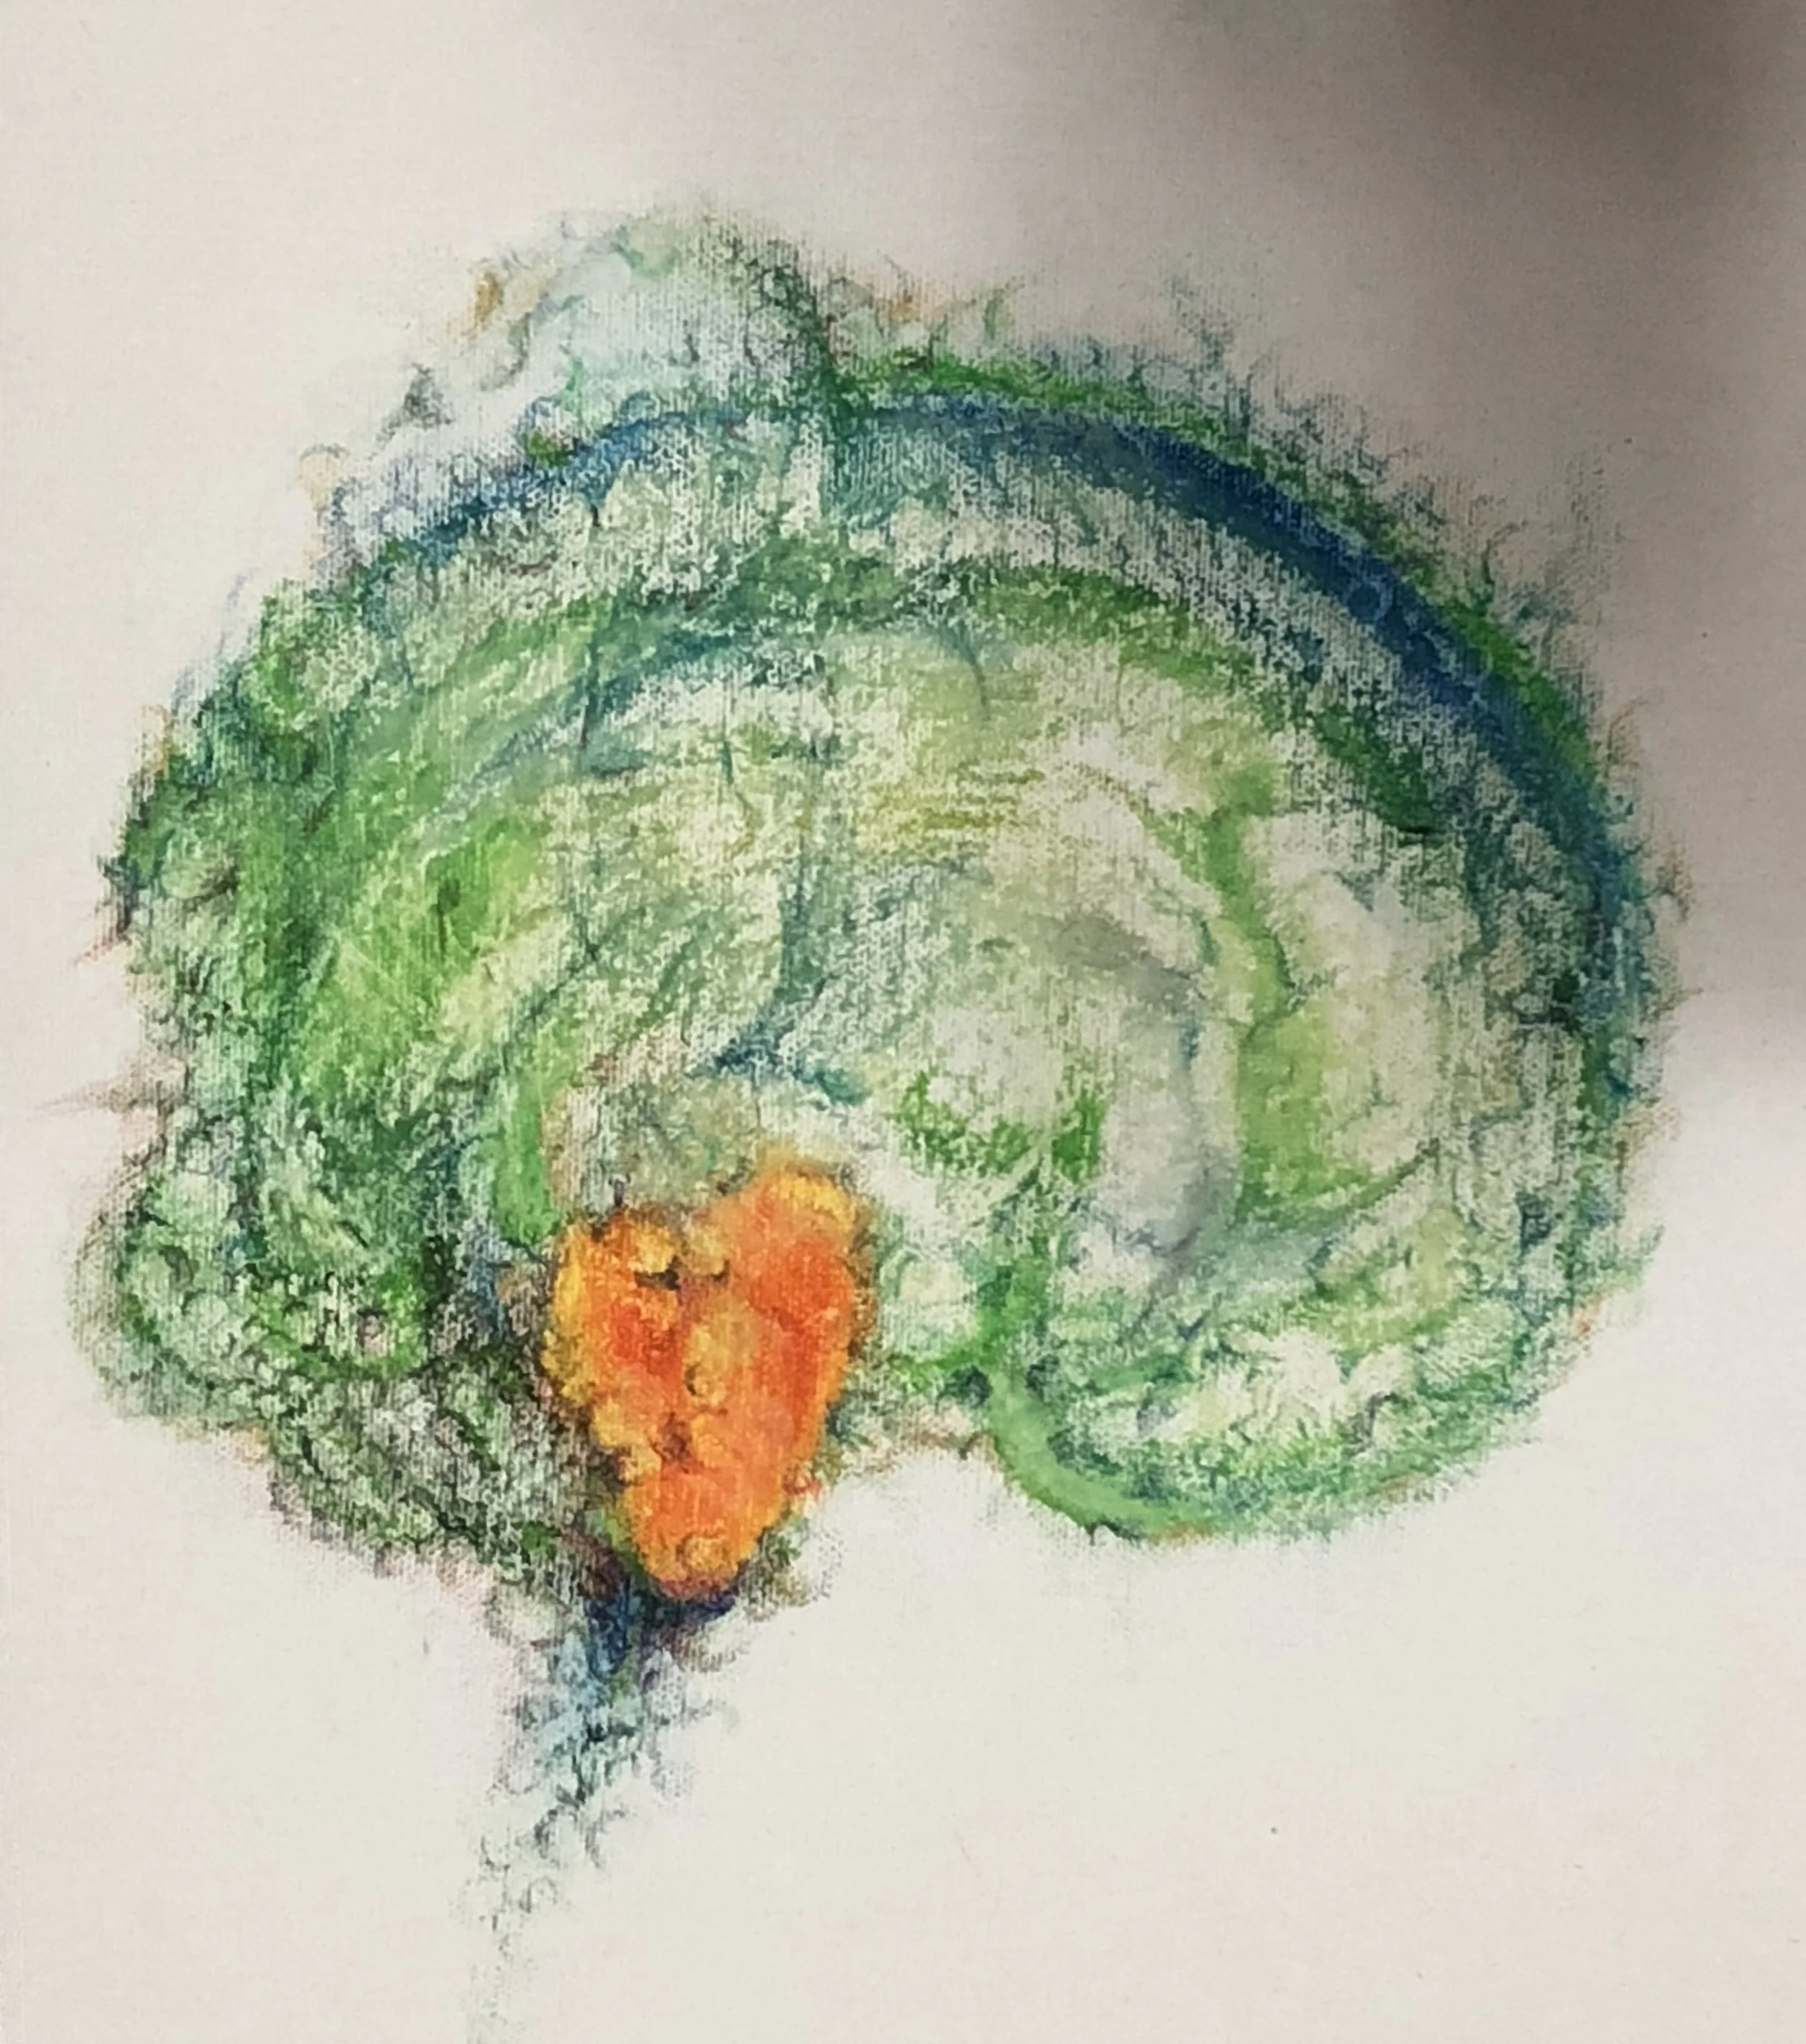

腦梗(Cerebral infarction)